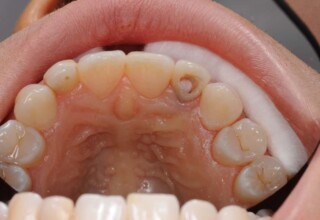

Αποκατάσταση Οπίσθιου Απονευρωμένου Δοντιού με Ανασύσταση Σύνθετης Ρητίνης

Η συνήθης αποκατάσταση ενός απονευρωμένου οπισθίου δοντιού είναι με μια στεφάνη. Ο κύριος λόγος είναι η προληπτική προστασία από κάταγμα και την επακόλουθη εξαγωγή. Σε πολύ συγκεκριμένες περιπτώσεις όπου εξειδικευμένα κριτήρια (κυρίως η ποσότητα της εναπομείνουσας οδοντικής ουσίας) ικανοποιούνται ή όταν η οικονομική δυνατότητα του ασθενή το επιβάλει, μια εκτεταμένη ανασύσταση συνθέτης ρητίνης μπορεί ν’αποκαταστήσει την αισθητική και λειτουργικότητα του δοντιού.